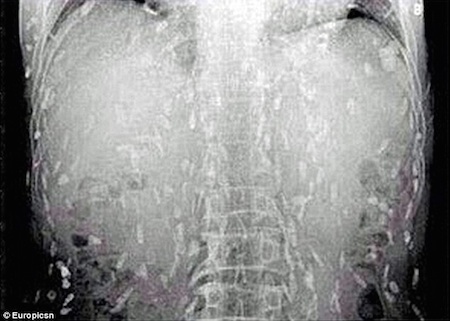

Ах, суши …Считается одним из самых причудливых продуктов во всем мире, их популярность взорвалась в течение последних нескольких десятилетий. Но, для одной неудачной китайской закусочной, он получил больше, чем взрыв аромата, когда он в последний раз отправился в суши-ресторан и заказал сашими. Суши были заполнены личинками ленточных червей.

После того, как у него возникли поразительные симптомы, включая расстройство желудка и зудящую кожу, неудачный энтузиаст суши попал в больницу. В Народной больнице Гуанчжоу № 8 в провинции Гуандун он, наконец, получил лечение от заражения лейкемией. Инцидент, безусловно, один для книг, основанный на графических рентгеновских снимках ужасающей болезни. Хотя человек мог умереть от неудачного кризиса здоровья, он получил отличный уход из больницы, а затем выздоровел. Надеюсь, он в следующий раз пропустит сашими.

После того, как его отправили в больницу, выяснилось, что у него была паразитарная инфекция